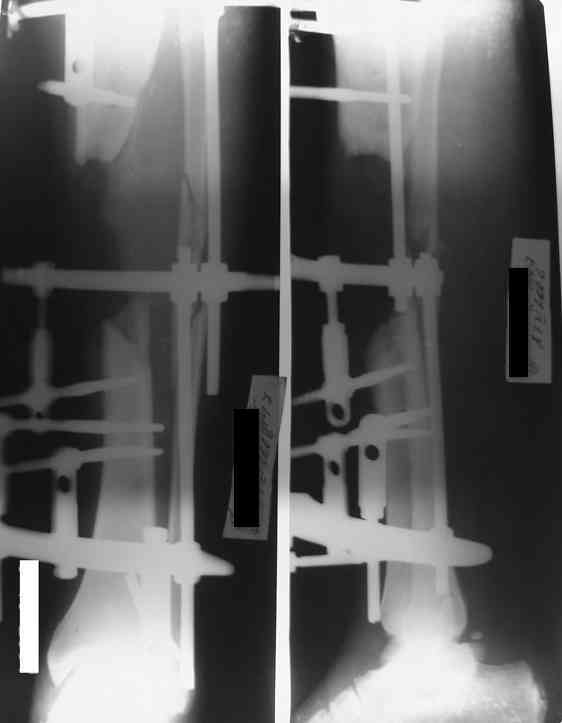

Re: Дефект и остеомиелит tibia

Доводим также к сведенью что дистальный межберцевый синастоз уже состоялся, ложный сустав малоберцевой кости в с/з. Учитывая так же отсутстаие нормального обеспечения больного в послеоперационном периоде мы склоняемся к аппарату внешней фиксации.

Как дополнение высылаю снимки и фото конечности, чтобы Вы могли оценить состояние м/т, и течение заболевания.